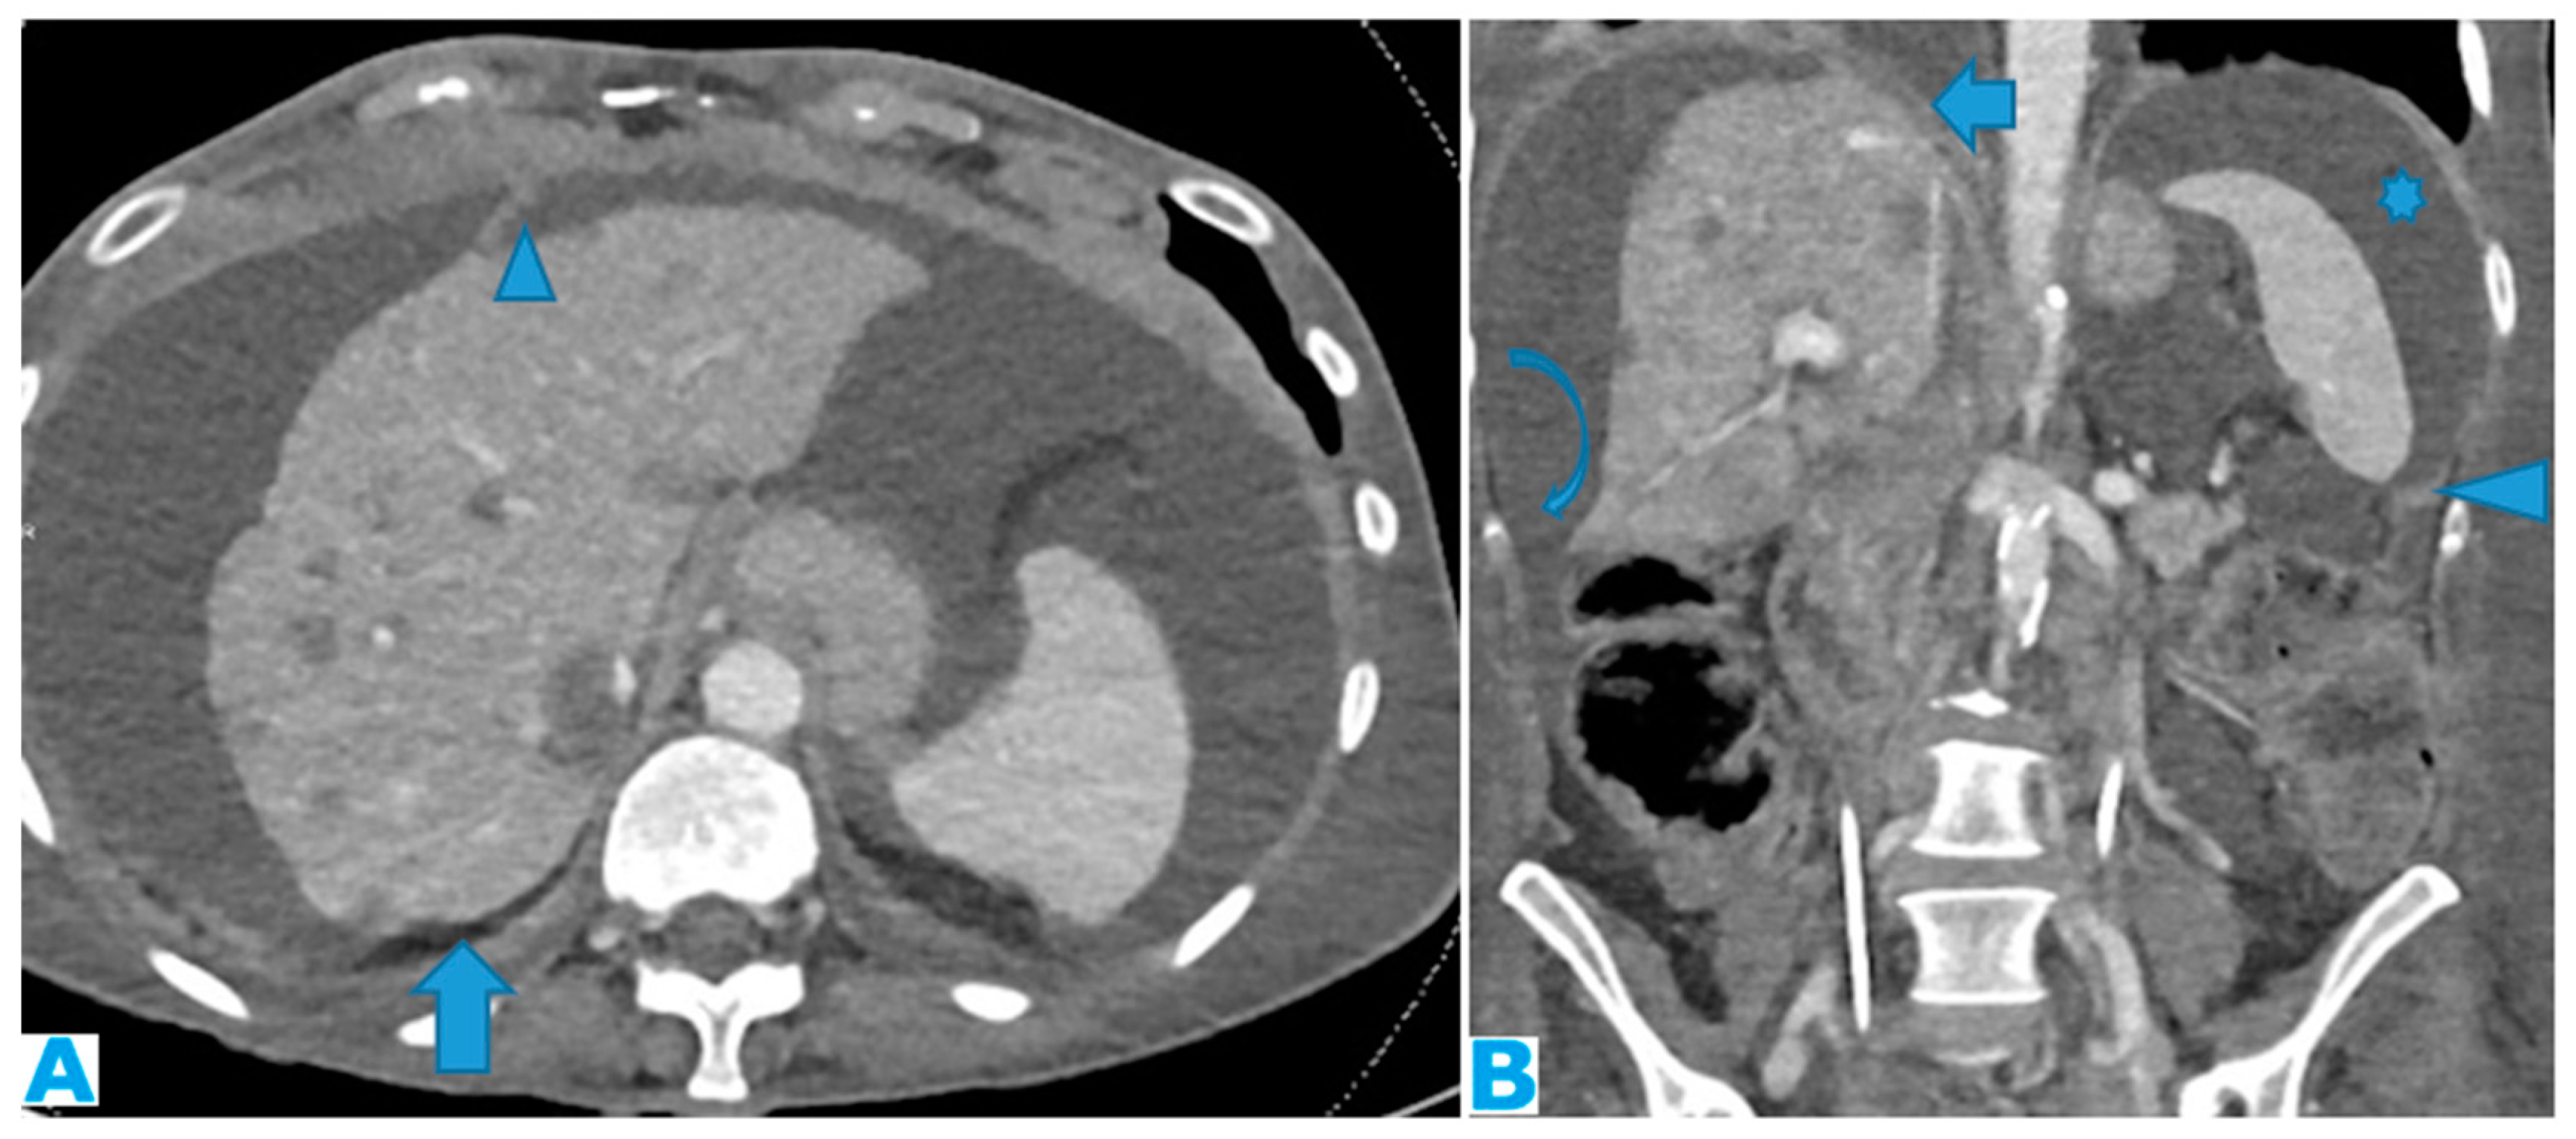

Axial CE-CT (A) and coronal MPR (B). Massive ascites, helpful to differentiate the peritoneal spaces. Observe on A how the posterior margin of the diaphragm (arrow) is not covered by the parietal peritoneum as it is directly in contact with the retroperitoneal fat. The attachment sites of ligaments on the diaphragmatic surface are not covered by peritoneum; Identify on A the falciform and on B, the phrenicocolic ligaments (arrowhead). Notice on B how the phrenicocolic ligament partially separates the left parietocolic gutter from the left subphrenic space (*), whereas the right parietocolic gutter fully communicates with the right subphrenic space (curved arrow). Identify the bare area of the liver on B (arrow), an area directly attached to the diaphragm by connective tissue, thus not covered by peritoneum as neither is its diaphragmatic attachment site.